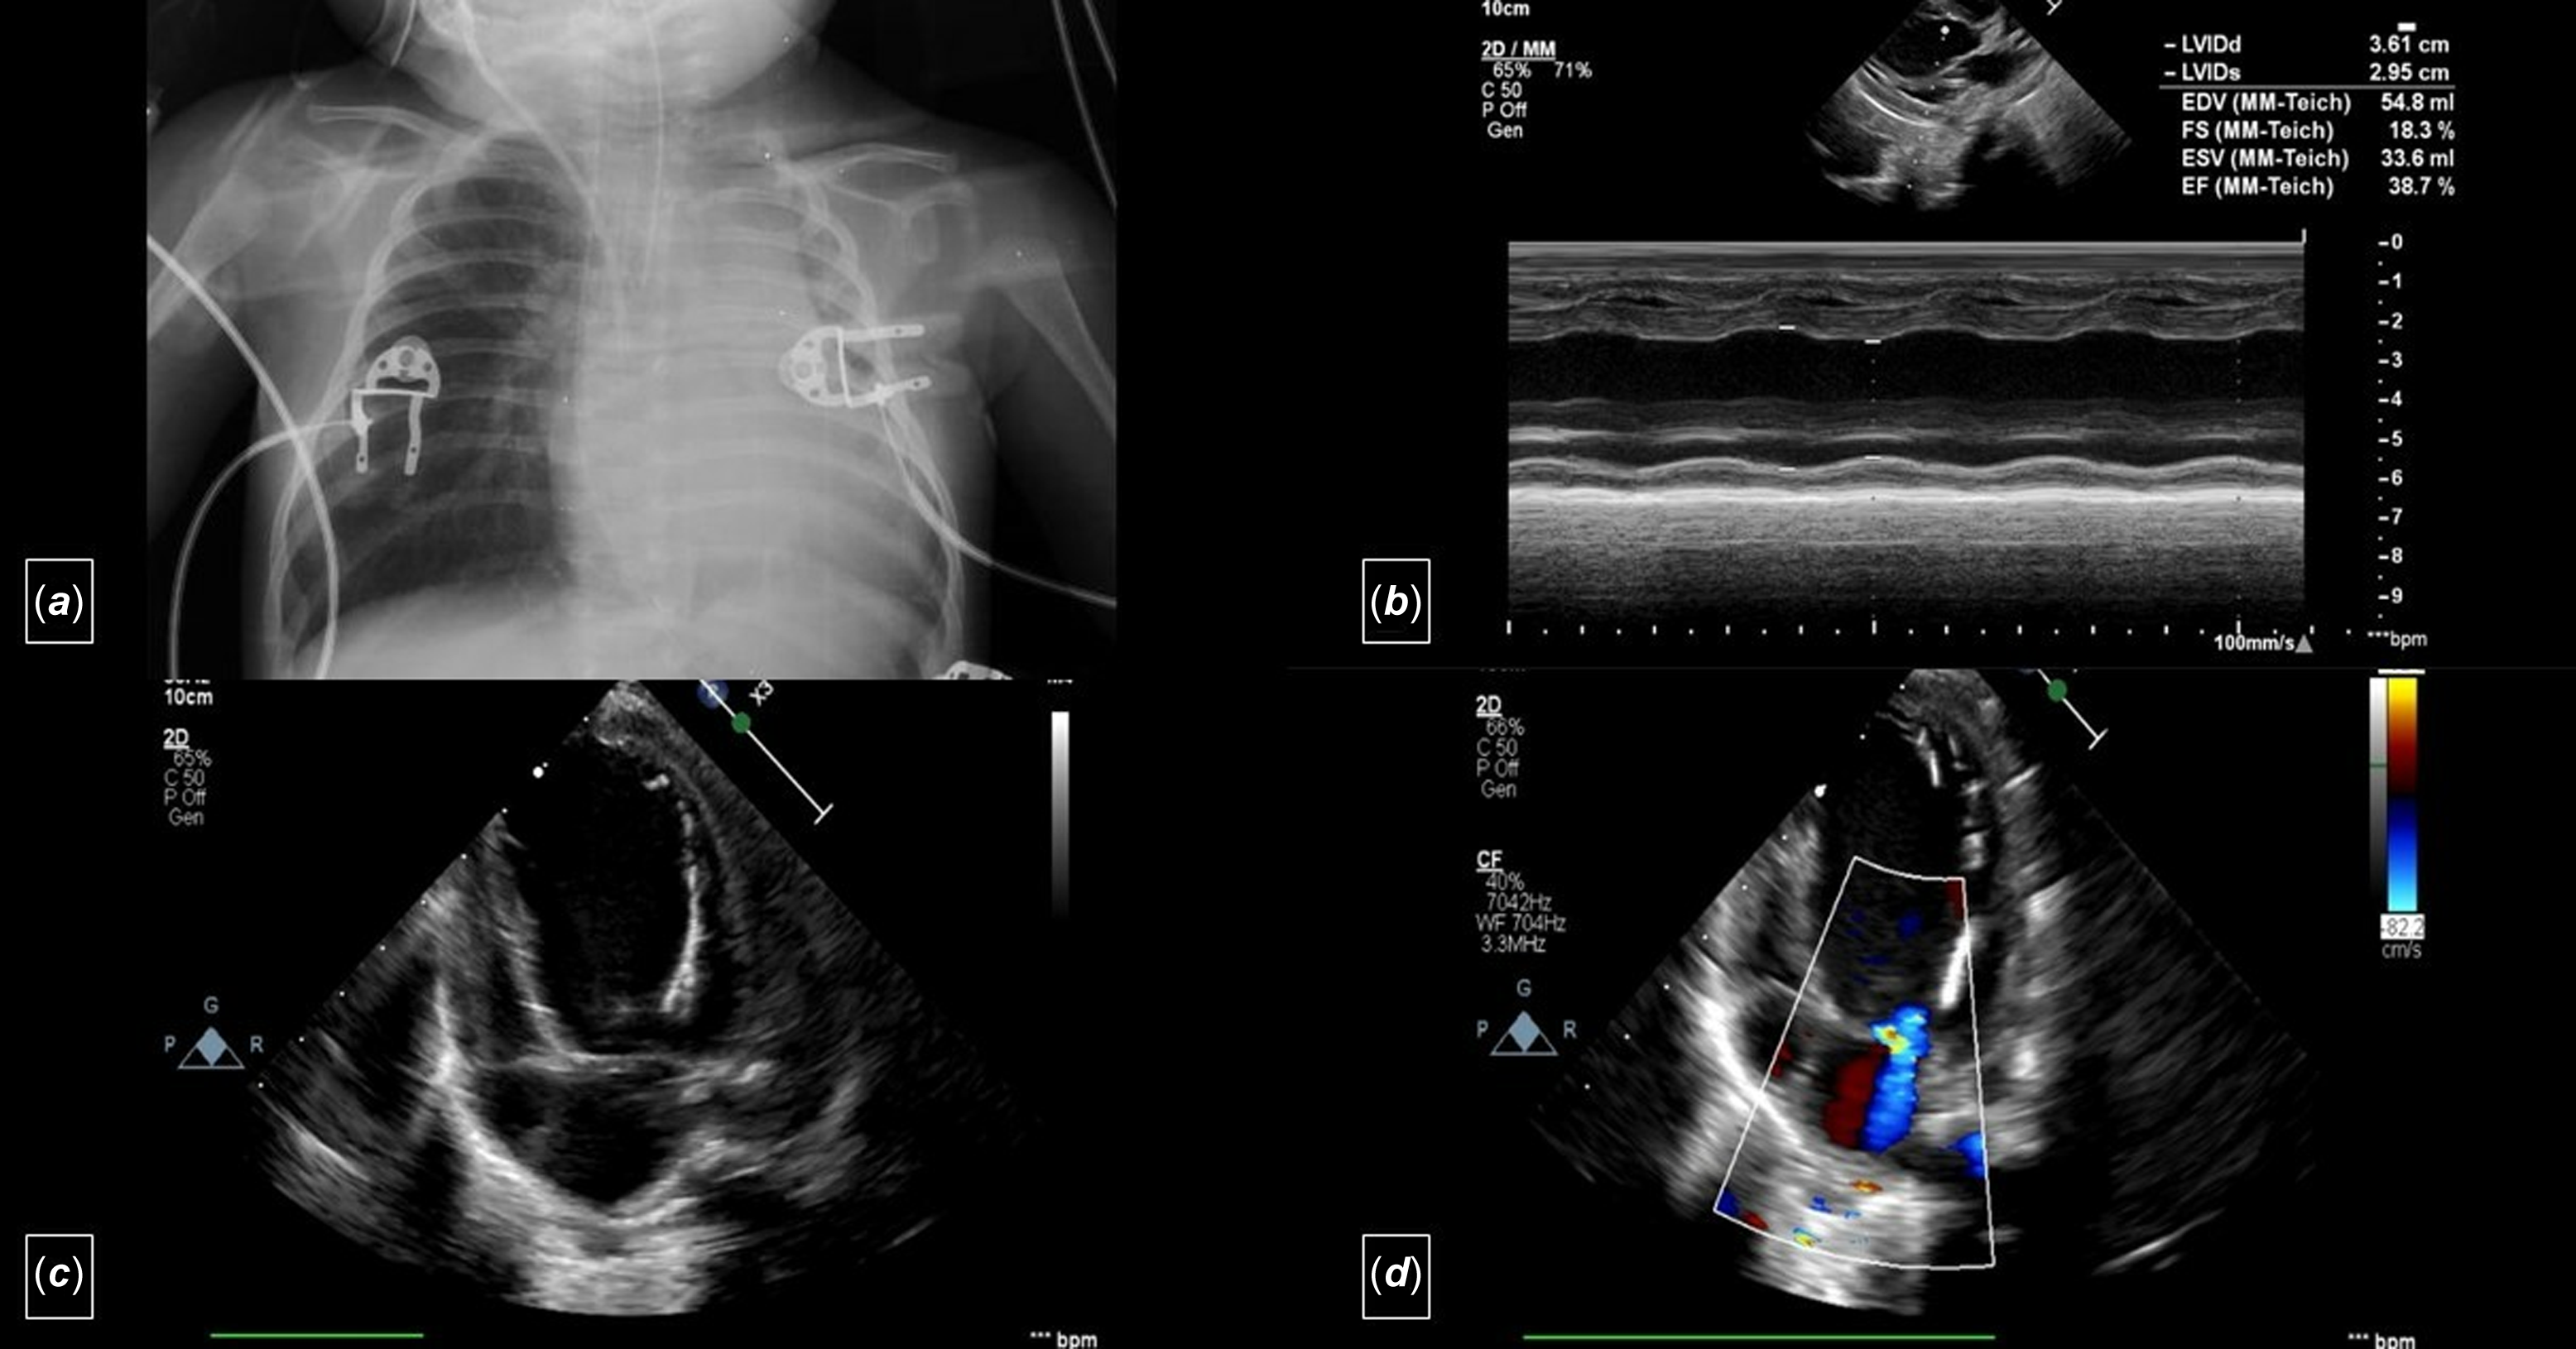

A two-month-old, 4.5 kg weight girl diagnosed with anomalous left coronary artery from the pulmonary artery and severe congestive heart failure was referred for surgery. Echocardiography revealed dilation of the left ventricle, reduced left ventricular ejection fraction ( 38%), a moderate degree of mitral regurgitation, and endocardial fibroelastosis (grade 2) (Figure 1). The electrocardiography showed pathological Q waves in the lateral lead (notable in aVL) (Figure 2a). Cardiac catheterisation demonstrated the anomalous origin of the left coronary artery.

Figure 1. a. Telecardiography shows cardiomegaly. b: M-mode echocardiography (transthoracic echocardiogram) from a parasternal long-axis view showing dilatation of the left ventricle and decreased cardiac function. c: Apical four-chamber view (transthoracic echocardiogram) showing dilatation of the left ventricle and endocardial fibroelastosis (grade 2). d: Apical four-chamber view (transthoracic echocardiogram) showing the moderate degree of mitral regurgitation.